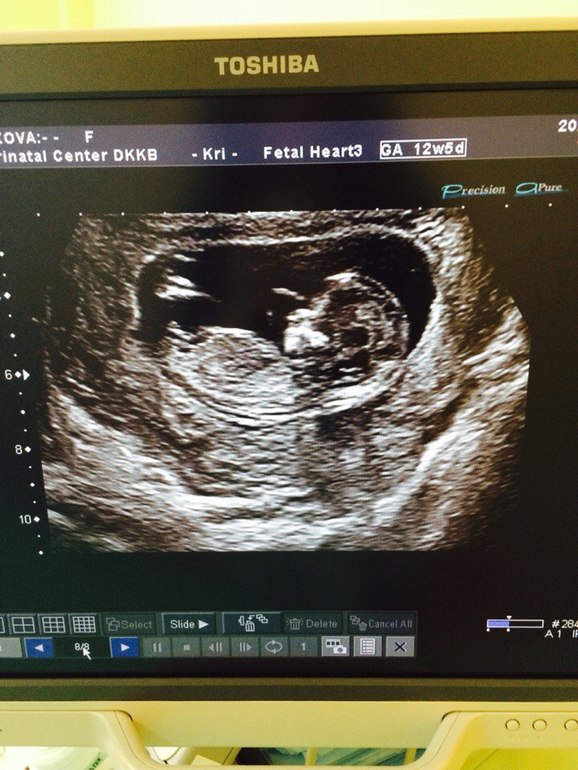

где на снимке видно пол ребенка?)

на скрининговом узи сказали похоже на девочку, я полистала сайты, там показано где какая часть тела, получилось так что увидела я тут мальчика. подскажите пожалуйста, может кто то тоже видит?)

Именно по этой фотографии мне кажется мальчик,но ваше у узисту значит было виднее,раз он предположил девочку)в этом случае сходите на внеплановое недель в 16😉

хорошие узисты на хороших аппаратах верно определяют пол на 1 скрининге. По направлению отросточка на фото — похоже на девочку.

Не факт, что именно пот ЭТОМУ снимку вам узист сказал что дева. Они ж под разными углами смотрят и предполагают. А этот снимок просто получился удачно))))) вот вам его и показали. По этому списку ничего не понятно, кто тут лежит!!!